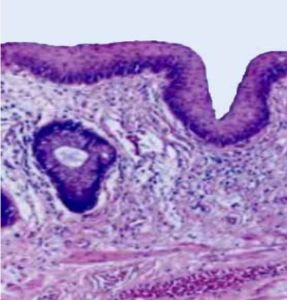

External Anal Margin

histology-external-anal-margin

• keratinized

• thick 90-100 um

• dry

• resistant